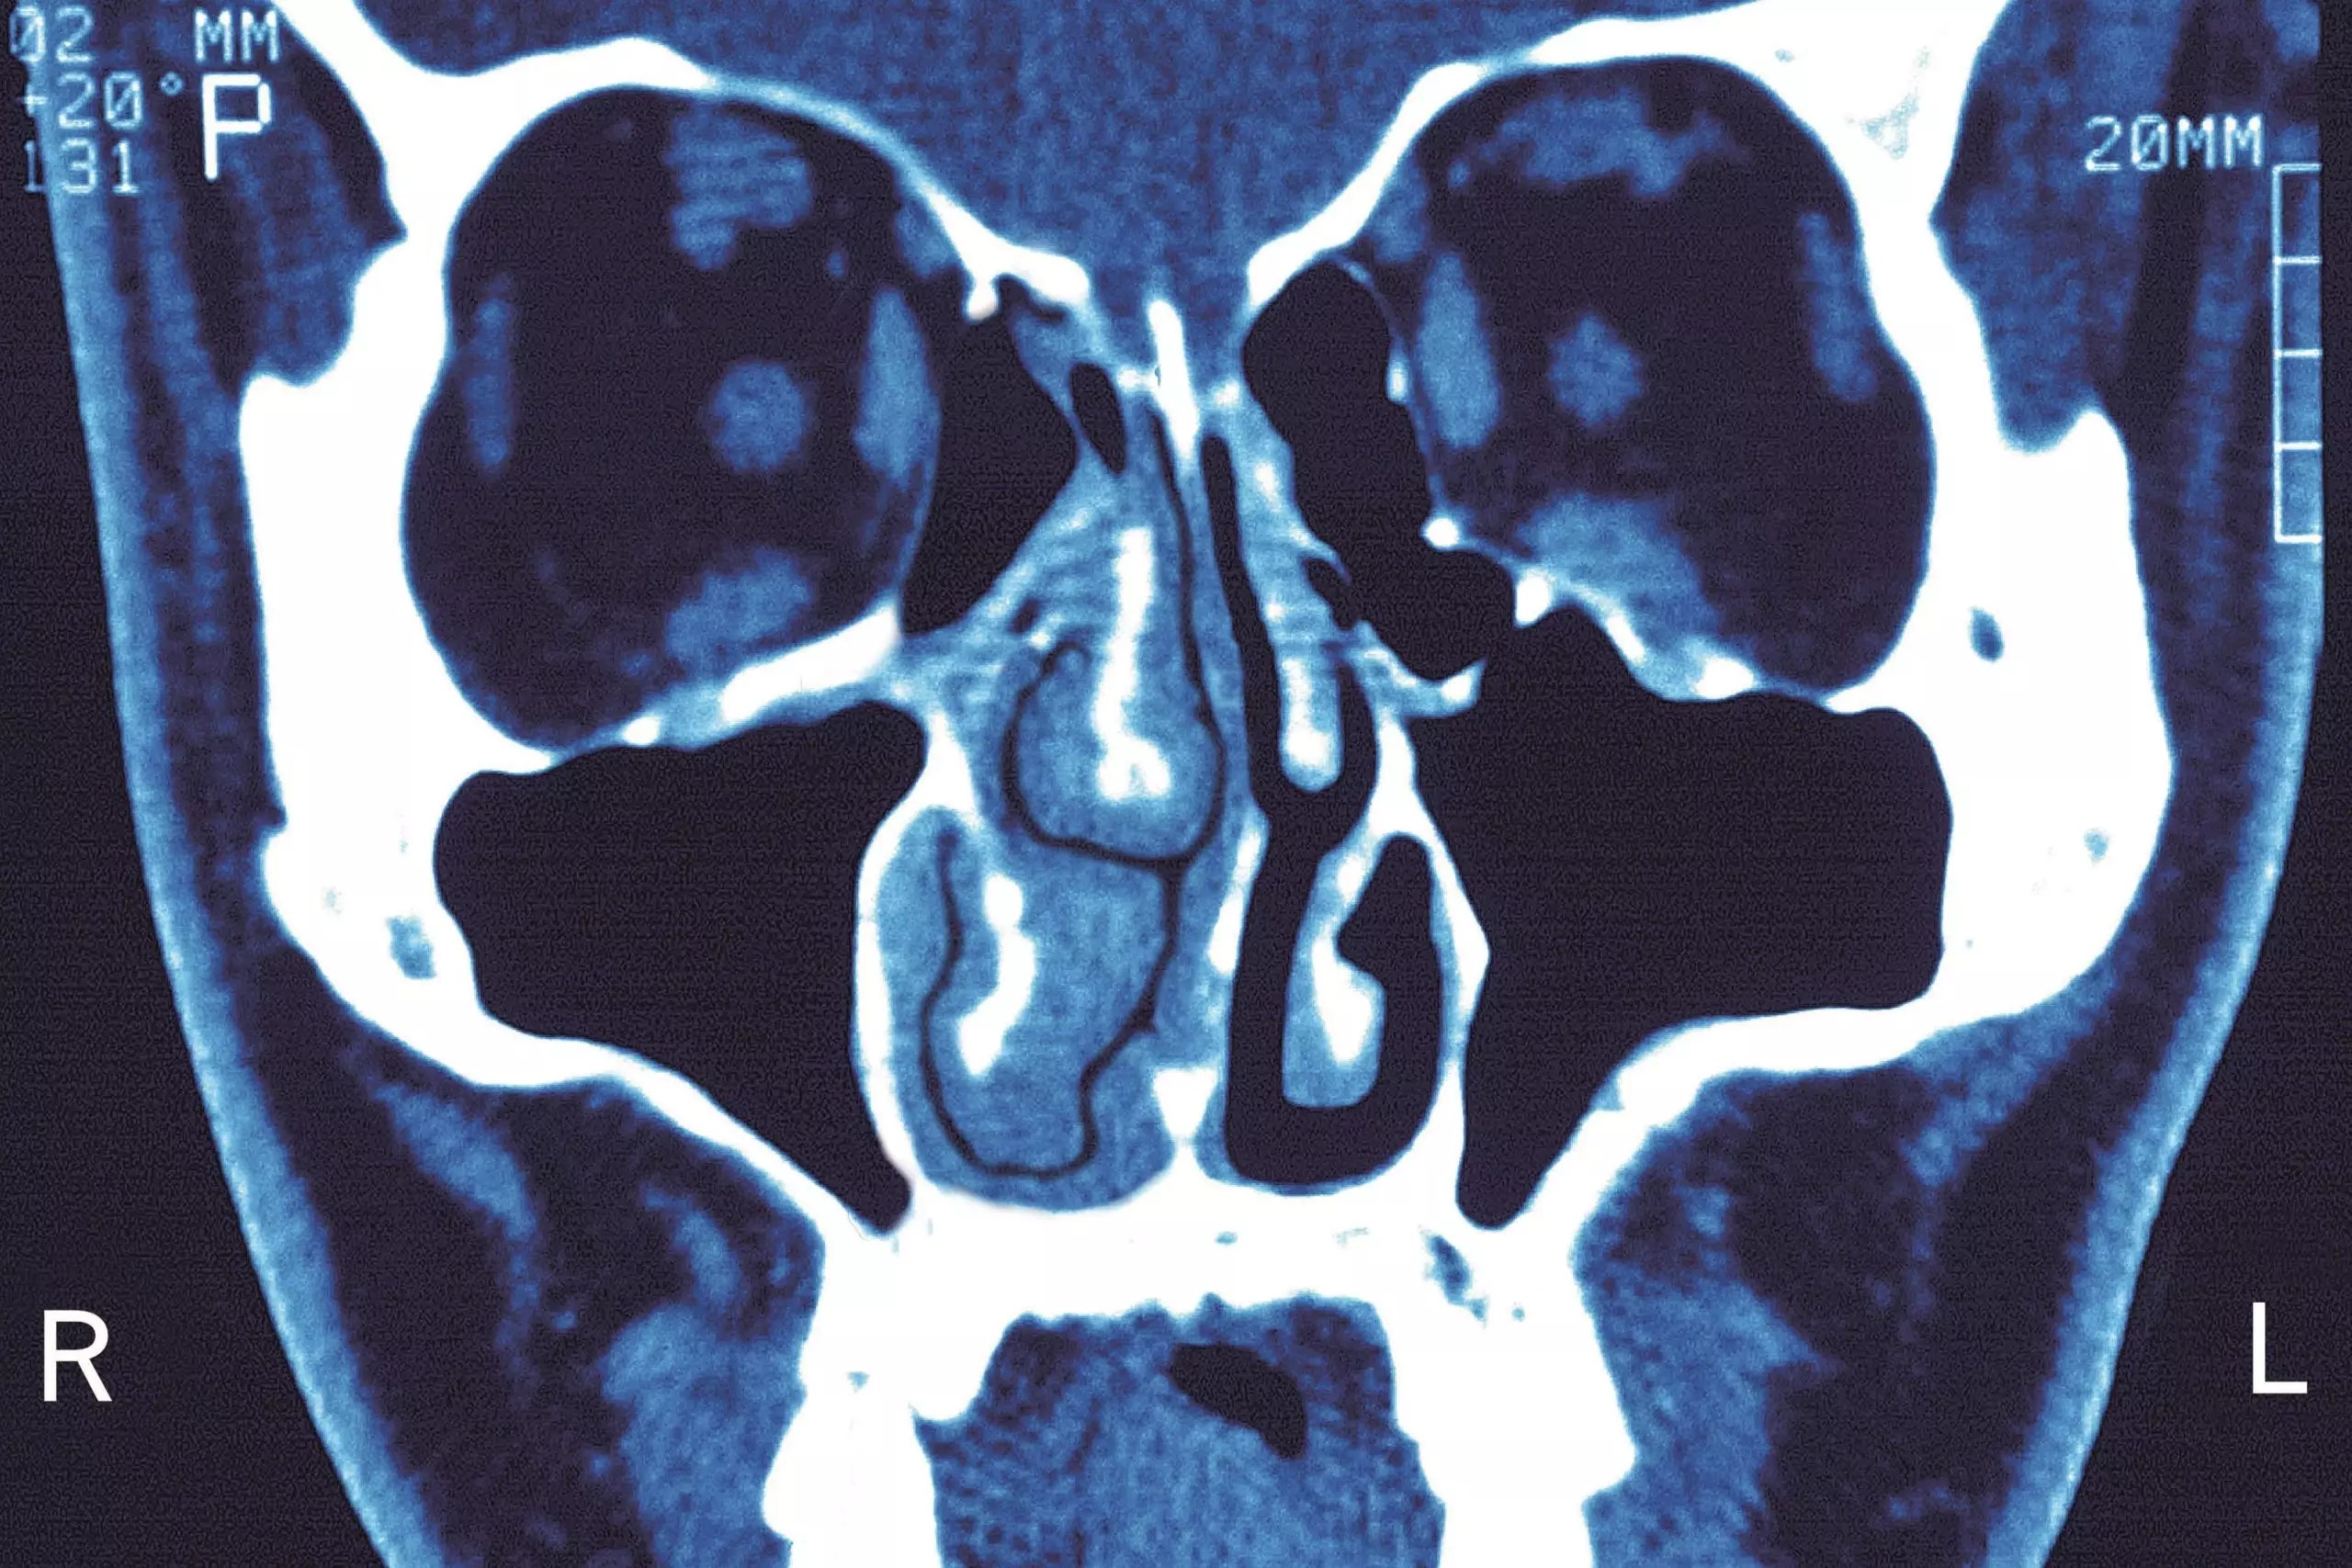

Oral Steroid Treatment For Sinusitis . However, research shows that it may be best left for severe cases. Prednisone, an oral steroid, may be prescribed for some sinus infections. If your sinus infection is mild, prednisone may not make you feel better any faster, and its side effects and risks will likely outweigh any possible benefits. Oral corticosteroids as a monotherapy appear to be ineffective for adult patients with clinically diagnosed acute. They work by controlling the. Short courses of oral corticosteroids are a widely used treatment for chronic rhinosinusitis.